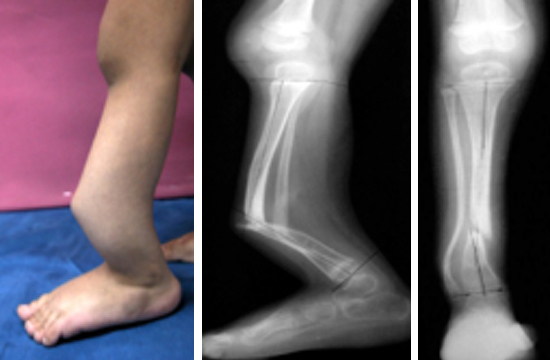

KTP’nin doğal gelişiminde tedavi edilmezse iyileşmeyen psödartroz, progressif kısalık, ayakbileğinde valgus deformitesi bulunur. Tedavide başlıca psödartrozun iyileştirilmesi amaçlanmalıdır.

Bu tekniğin amacı hastada mevcut olan psödartroz, kısalık ve deformiteden oluşan tüm patolojilerin tek bir ameliyat ile giderilebilmesidir. Böylece postoperatif refraktür, kısalık, fibular psödartroz tek bir cerrahi girişimle tedavi edilebilir. Hastalar birer aylık aralıklarla diz ve ayak bileği ROM, ağrı, çivi dibi enfeksiyonu, yeni oluşan rejeneratın kalitesi gibi klinik kriterler açısından değerlendirilir. Radyolojik olarak da MPTA ( medial proksimal tibial açı), LDTA (lateral distal tibial açı),kısalık farkı, İM çivinin migrasyonu tetkik edilmesi gereken başlıca kriterlerdir.

Klinik tecrübemiz hastalarda ortalama kaynama süresini 5 ay olarak vermektedir. Eksize edilen spesimenlerin patolojik tanısı hemen daima fibröz hamartoma olarak gelmiştir.